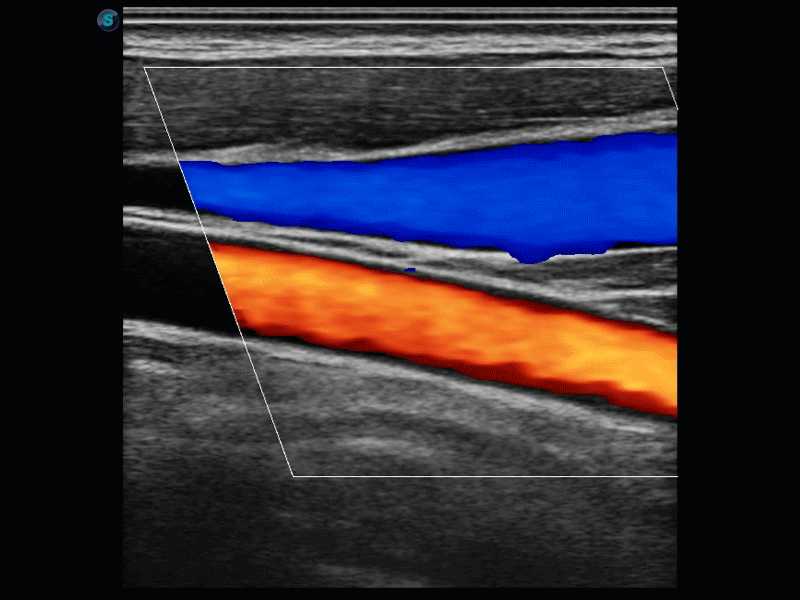

開立醫(yī)療通過不斷的技術(shù)創(chuàng)新,為大眾的生命健康提供持續(xù)關(guān)愛。P12 Plus采用全新一代超聲成像平臺,新平臺旨在將真實(shí)還原組織解剖結(jié)構(gòu)作為首要目標(biāo)。平臺采用全新集成化硬件模塊,搭載新一代芯片,系統(tǒng)性能得到大幅提升,為您的診斷提供了豐富的臨床信息。優(yōu)異的圖像表現(xiàn),豐富的探頭配置,全面的應(yīng)用功能,為您日常診斷提供了可靠的助手。

P12 Plus

彩色多普勒超聲診斷系統(tǒng)